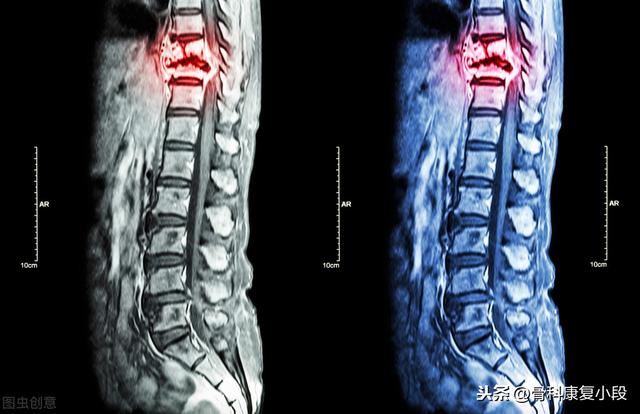

骨転移の磁気共鳴画像法

胸椎に発生した骨転移性癌を示す。

Dr.シャドウです。骨転移とは、がんが進行した状態のことで、がん細胞が血流にのって骨に転移し、骨に定着・増殖することで、溶骨性骨破壊や骨芽細胞性骨密度増加を引き起こします。腰痛や下肢痛のために進行した肺がんが発見されるがん患者が多いのは残念なことです。

46歳の男性が、腰の持続的な痛みのために受診した症例があった。腰痛は椎間板ヘルニアと考えられた。レントゲンを撮ったが異常は見られなかった。わずかな骨破壊を起こす骨転移はレントゲンでは見えないし、椎間板ヘルニアもレントゲンでは見えない。だから、転移の可能性については特に考えなかった。1週間後、それでも改善が見られないのでCTを撮りに来たところ、腰椎が食べられていた。 このような画像を見て、画像診断医は転移の可能性を考えるに違いないと思い、胸部CT検査をするよう患者に勧めたところ、案の定、肺に腫瘤があり、肺がんの骨転移と考えられ、後日病理検査で確認された。